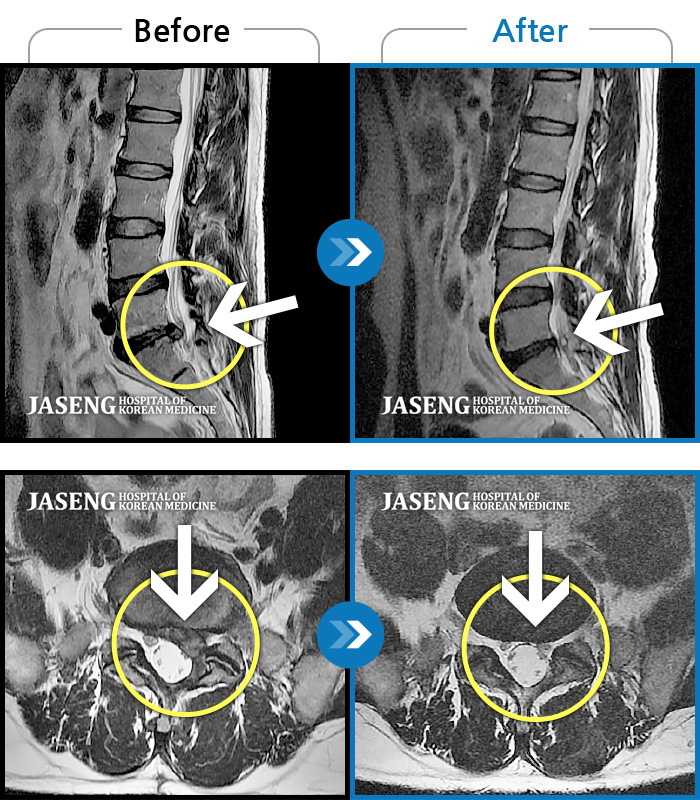

허리디스크

일산 · 배영현 원장

허리, 좌측 골반, 좌측 다리 통증 및 저림이 심해서 정상적인 일상생활이 힘든 상태

촬영시기

2021.10.04 ~ 2022.11.18

2022.12.02